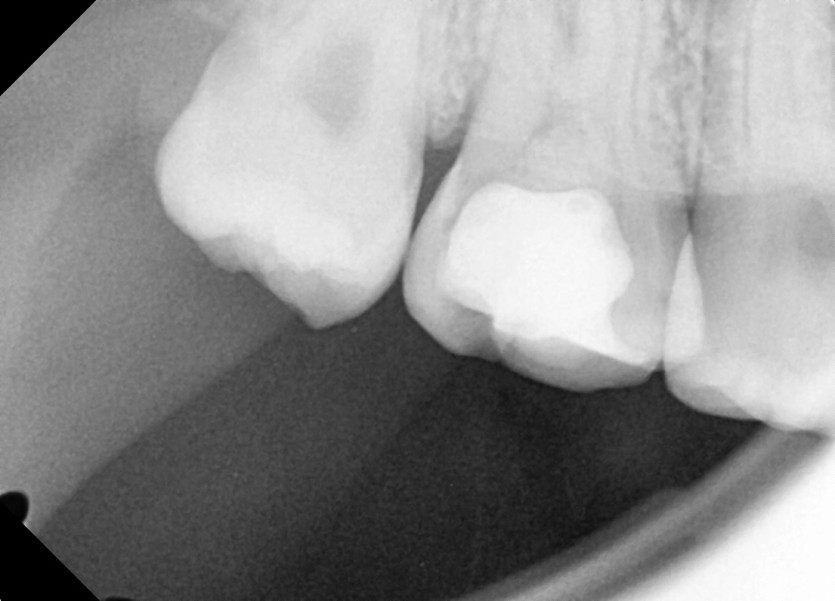

#18,48 사랑니 발치

구강 외과 전문의가 당일 발치했습니다.